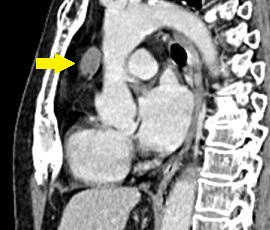

[気管支原性嚢胞] 手術:胸腔鏡下縦隔腫瘍手術

CT画像